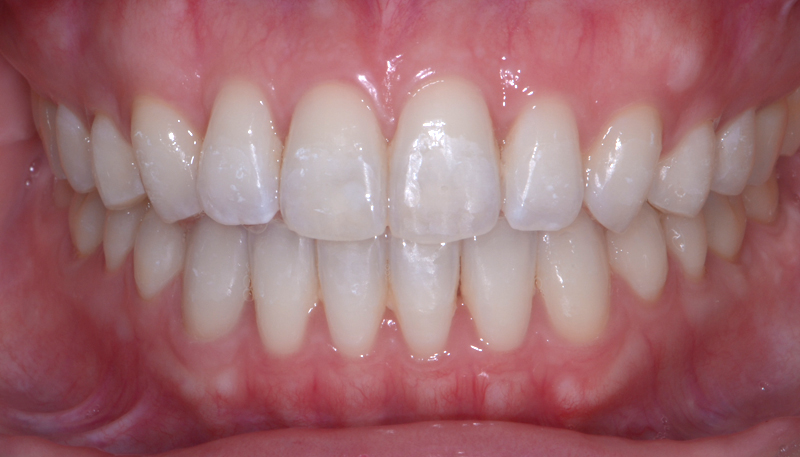

当院での矯正治療症例